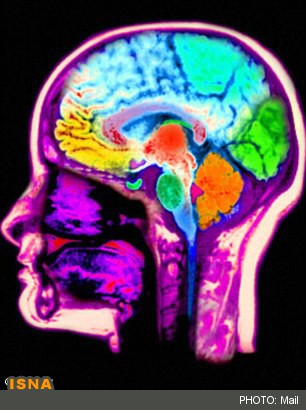

تیمی از دانشمندان شرکت دارویی Heptares Therapeutics واقع در هرتفوردشایر انگلستان، از یکی از قدرتمندترین ماشینهای پرتو ایکس برای مطالعه غده هیپوفیز مغز استفاده کردند.

مدتهای طولانی است که تصور میشود این غده، استرس، افسردگی و اضطراب را با ترشح مواد شیمیایی استرسزا کنترل میکند.

هماکنون دانشمندان دریافتهاند چنین واکنشی توسط CRF1 واقع در غشاهای بیرونی سلولهای هیپوفیز ایجاد میشود.

پروتئین CRF1 در سلولهای هیپوفیز قرار دارد و مولکولهای استرس را که خود توسط هیپوتالاموس شناسایی شدهاند، شناسایی میکند.

هیپوتالاموس بخشی از مغز و تولیدکننده هورمونهایی است که دمای بدن، گرسنگی و مزاجها را کنترل میکنند.

زمانی که این بخش یکی از این مولکولها را گیر میاندازد، سلول والد را برای ترشح هورمونهایی که منجر به استرس و اضطراب میشود، فعال میکند.